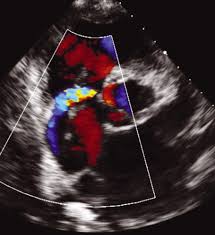

심장 초음파로는 혈액의 역류를 막아주는 4개의 판막이 잘 열리고 잘 닫히는지, 구멍 등 이상 소견은 없는지, 혈액의 역류는 없는지 등을 확인할 수 있다고 한다.

심장판막질환 중 최근 급격히 증가되고 있는 대동맥판막협착증은 대동맥판막이 노화돼 판막이 딱딱해지고 좁아지면서 잘 나가던 혈액이 못 나가게 되는 것으로 전신 쇠약, 흉통, 어지럼, 실신, 호흡곤란 등이 나타날 수 있다고 한다.

나이 들면 흔히 나타나는 증상이라고 여기기 쉽지만 방치하면 심장기능이 점점 떨어지면서 사망위험이 높아진다. 실제로 대동맥판막협착증 방치 시 2년 내 사망률은 50%에 달한다고 알려졌다고 한다.